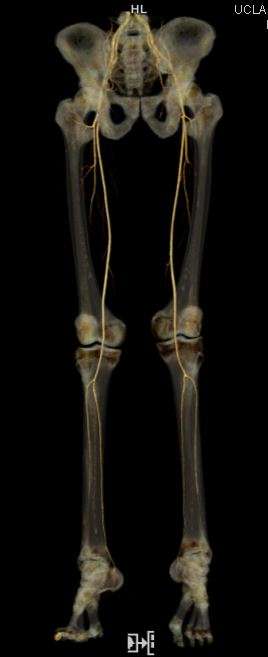

- Run-Off Visualization

Lower Extremity Runoff